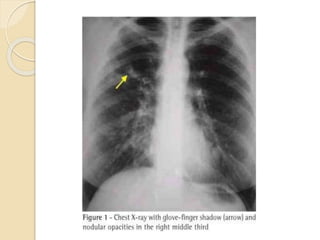

Radiologic Investigations

 Chest radiographic findings

 Transient changes

◦ Patchy areas of consolidation

◦ Radiologic infiltrates: toothpaste and gloved finger

shadows due to mucoid impaction in dilated bronchi

◦ Collapse: lobar or segmental

◦ Perihilar infiltrates may simulate adenopathy

 Permanent changes

◦ Parallel-line shadows representing bronchial widening

◦ Ring-shadows 1–2 cm in diameter representing dilated

bronchi en face

◦ Pulmonary fibrosis: fibrotic scarred upper lobes with

cavitation

CHEST 2009; 135:805–826

Fig. Chest X-Ray of ABPA patient with Consolidation and Finger like

shadow